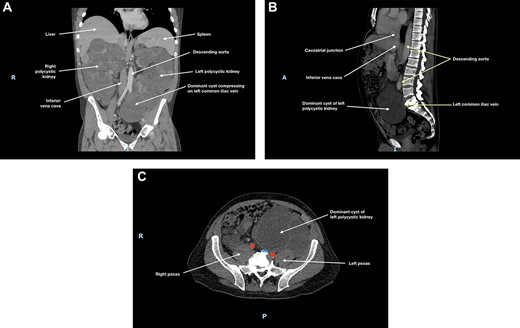

At 3-month follow-up, CT angiogram showed persistent IVC compression by the right polycystic kidney, with near-complete effacement (Fig. 2). There was no thrombus distal to this compression and the patient was asymptomatic. May-Thurner syndrome was ruled out. As the right kidney had been found to cause IVC compression and to extend into the pelvis, an elective right nephrectomy was performed to prevent further thromboses in the right-sided deep venous systems and to create space for subsequent transplantation. The right kidney measured 270 × 170 × 150 mm and weighed 3098 g. There was extensive cystic alteration with fibrosis and tubular atrophy; no malignancy was identified.

(A) Coronal, (B) sagittal and (C) axial views of the patient’s CT angiogram at 3 months post-left nephrectomy, showing persistent inferior vena cava compression by the right polycystic kidney, with near-complete effacement; in (c), the inferior vena cava is depicted in blue and the descending aorta is depicted in red.